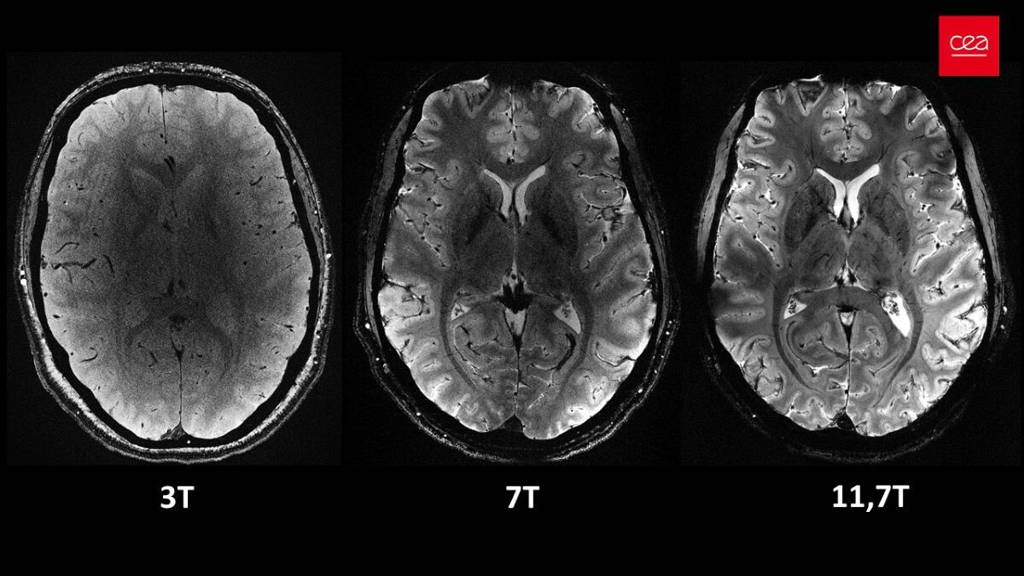

Het Commissariat à l'énergie atomique et aux énergies alternatives (CEA) is een toonaangevende Franse overheidsorganisatie die zich richt op onderzoek, ontwikkeling en innovatie. Opgericht na de Tweede Wereldoorlog, in 1945, speelt het CEA een grote rol in het bevorderen van wetenschappelijke kennis en het stimuleren van technologische ontwikkeling in Frankrijk en daarbuiten. De organisatie presenteert nu de Iseult MRI-scanner. Deze bleek in staat om in vier minuten tijd de meest indrukwekkende anatomische hersenbeelden ooit te produceren. Met 11,7 Tesla overtreft de machine de huidige ziekenhuisscanners (1,5 of 3 tesla), niet alleen op het gebied van snelheid maar ook in het geven van details in de beelden.

Ongelooflijke hersendetails

Op de scans van de hersenen zijn ongelooflijke details zichtbaar tot wel 0,2 millimeter, waaronder zeer fijne bloedvaatjes in het brein. Het detailniveau is indrukwekkend, want reguliere scanners hebben een resolutie van ongeveer 1 millimeter. De grote mate van detail geeft nieuwe inzichten in de anatomie, verbindingen en activiteit van de hersenen. Het stelt onderzoekers in staat om fundamentele vragen over hersenmechanismen te beantwoorden. Bovendien opent het nieuwe onderzoeksmogelijkheden naar de diagnose en behandeling van neurodegeneratieve ziekten zoals Alzheimer en Parkinson. Tot slot biedt deze krachtige machine aanknopingspunten voor toekomstige studies, die kunnen helpen om de effectiviteit van medicijnen, zoals lithium voor bipolaire stoornissen, beter te begrijpen.